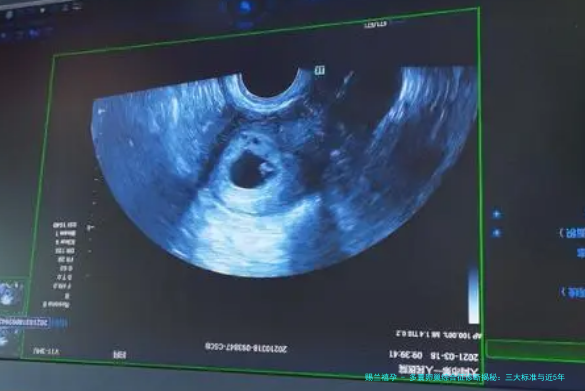

标准三:超声显示多囊卵巢形态

第三个标准是通过盆腔超声检查卵巢形态,显示为多囊样改变,即一侧或双侧卵巢有12个或更多直径2-9毫米的卵泡,或卵巢体积增大(大于10毫升)。近5年,超声技术更先进了,如3D超声和人工智能辅助诊断,提高了检测精度。但2023年的指南强调,超声标准需要谨慎应用,因为年轻女性或服用避孕药的人可能出现假阳性。具体案例:张阿姨的女儿,20岁,体检时超声发现多囊卵巢,但进一步检查排除了PCOS,因为她没有其他症状。个人观点是,超声只是一个工具,不能单独下定论,必须结合前两个标准。这就像拼图——缺一块都不完整。